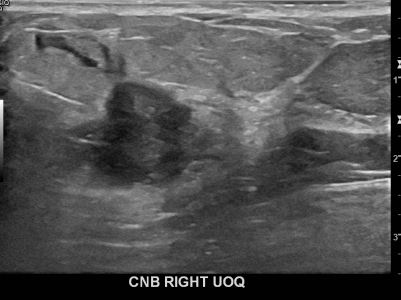

아산유외과개원후 648번째 유방암진단

상기환자 외부검사상 이상소견으로 내원하신 70대여성으로 우측유방의 의심스러혹

조직검사시행해 유방암 진단되었습니다.